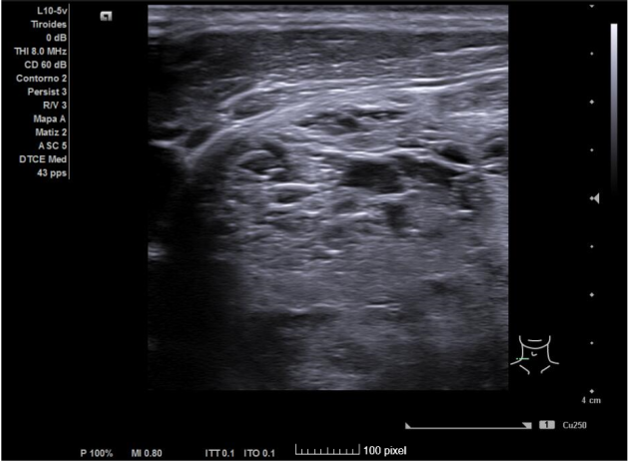

Hallazgos ecográficos

Ecografía clínica de tiroides: Glándula tiroides muy aumentada de tamaño. Istmo irregular de 20 mm. Lóbulos tiroideos desestructurados, aumentados de tamaño (siendo mayor el derecho) y presencia de múltiples nódulos, algunos anecogénicos y otros de estructura espongiforme. No se aprecia aumento de vascularización con modo Doppler que descarta situación de tormenta tiroidea.